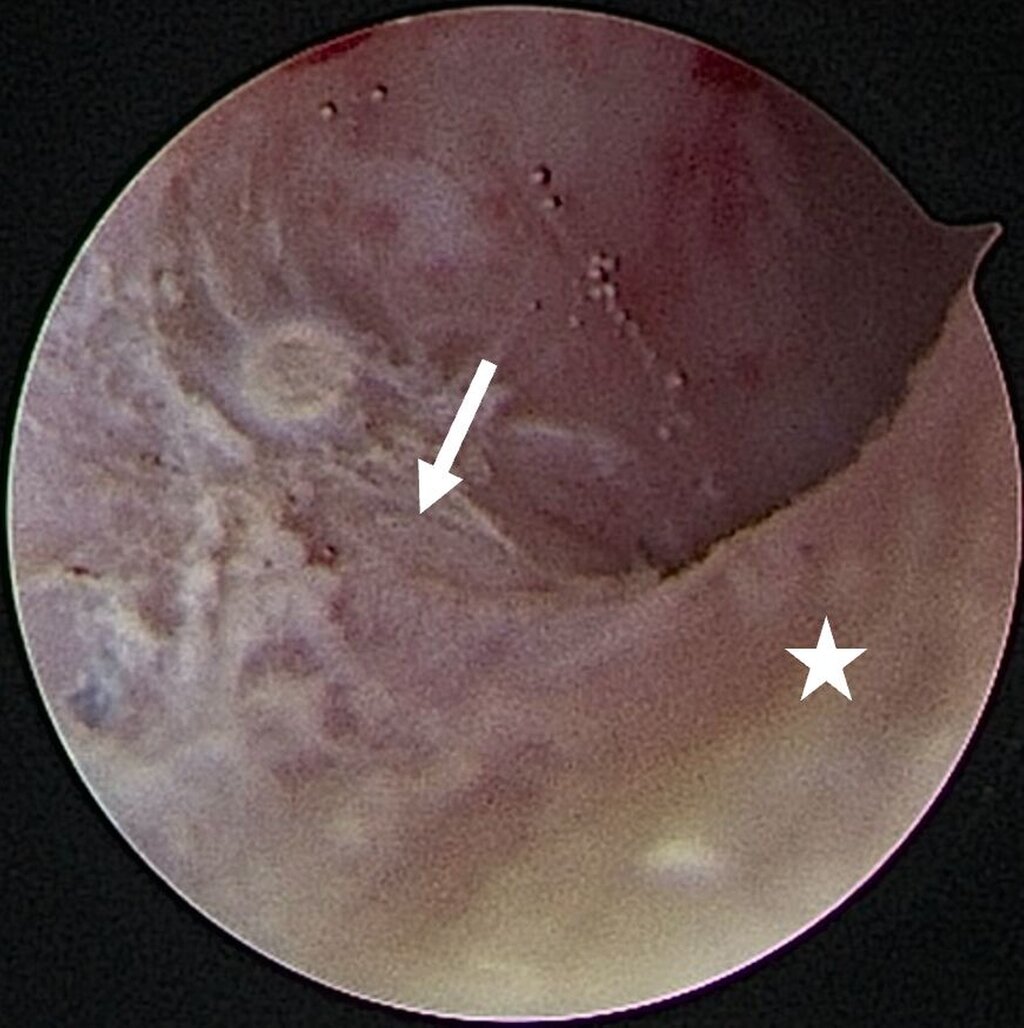

Eine Entzündung im Bereich der Gelenkkapsel (Synovitis) stellt eine häufige Ursache für arthrogen bedingte Beschwerden dar [Mercuri et al., 2025]. Neben der Darstellung des Gelenks und der Behandlung von Pathologien beruht ein positiver Effekt der Arthroskopie auf der Lavage des Gelenks. Dadurch können zum Beispiel proinflammatorische Mediatoren entfernt und intraartikuläre Adhäsionen gelöst werden [Soni, 2019]. Abbildung 2 zeigt die intraoperativen Befunde von zwei Patienten. Es wird jeweils der Übergang zwischen dem hinteren Aufhängungsband und der pars posterior des Discus articularis dargestellt.

Für die Kiefergelenksarthroskopie ist eine strukturierte Orientierung innerhalb des oberen Gelenkkompartiments essenziell. Hierfür haben sich die sogenannten „seven points of interest“ nach McCain etabliert (Abbildung 3) [Srouji et al., 2018]. Diese sieben anatomischen Referenzpunkte dienen der systematischen Beurteilung des Gelenks während des arthroskopischen Eingriffs. Zunächst werden das mediale synoviale Band und der Pterygoid-Schatten („pterygoid-shadow“) als Orientierungspunkte identifiziert. Es folgen die bilaminäre Zone – eine häufige Schmerzquelle – sowie die hintere Schräge der Gelenkeminenz. Die Beurteilung des Discus articularis gibt Auskunft über Verlagerungen und degenerative Prozesse. Es folgt die Beurteilung der intermediären Zone, die besonders anfällig für eine Perforation ist. Abschließend erfolgt die Begutachtung des vorderen Recessus. Dieser stellt den Eintritt der Punktionsstelle des Level-II-Zugangs dar [Srouji et al., 2018].